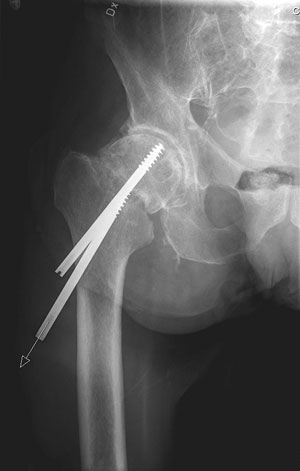

Förkortat och utåtroterat ben inger stark misstanke om höftfraktur, i detta fall högersidig dislokerad cervikal höftfraktur.

Cervikal höftfraktur hos 69-årig patient som halkat, opererad med skruvar. 2 år senare sökte han primärvården med smärta i höftleden. Röntgen visade caputnekros och skruvpenetration. Patienten remitterades till ortopedklinik och planerades för reoperation med extraktion av skruvar samt helprotes.